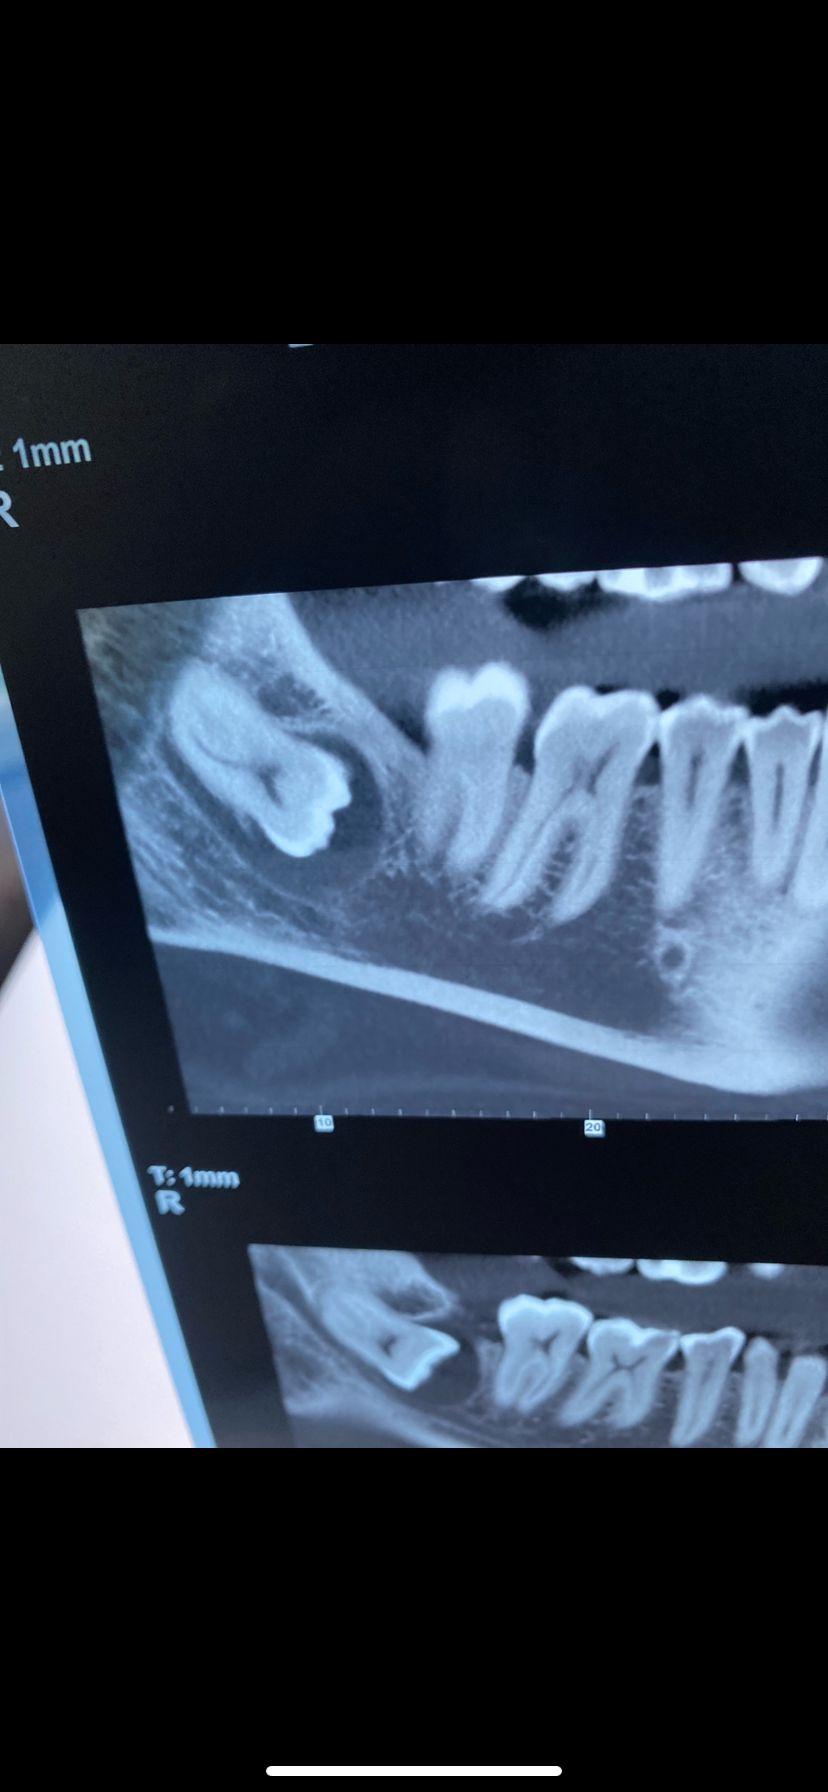

Vorrei avere un suo consiglio sull’estrazione del 48 incluso.

Al momento oltre ad una piccola ciste non ho nessun fastidio.

Pareri discordanti..c’è chi dice che va tolto,e chi invece ritiene rischioso.

Ma è davvero così complicato toglierlo nel mio caso?

Da 1 a 10 quanto è difficile?

Cosi da farmi un idea.